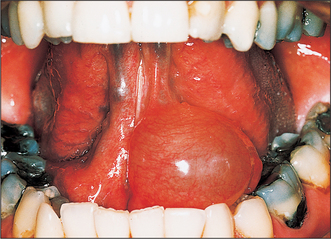

A ranula is a large mucocele arising from the sublingual gland, and typically presents as a large tense bluish swelling in the anterior floor of the mouth, often displacing the tongue (Fig. 14.8). However, the ranula may push its way through the midline mylohyoid dehiscence in the floor of the mouth and enter the submental space presenting as a midline swelling in the upper neck. This is the ‘plunging ranula’. The swelling may be entirely in the neck or the ranula may take on an hourglass shape with both submental and intraoral swelling. The treatment of a ranula must include excision of the sublingual gland.

image

Fig. 14.8 Ranulae are large mucoceles arising from obstruction of a sublingual gland.